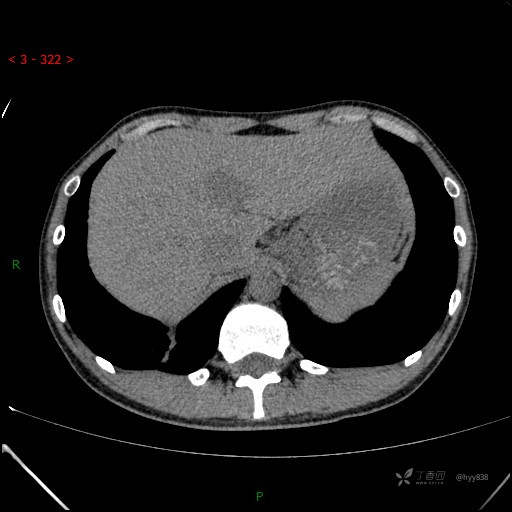

胸部CT平扫